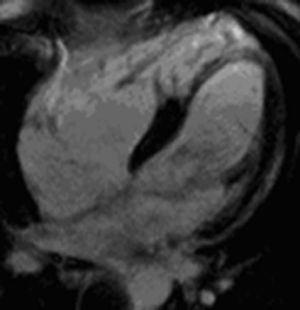

In our series, the most common trigger of ventricular arrhythmias was arrhythmogenic right ventricular dysplasia, criteria for which were found with a high probability in over a quarter of patients (Figures 1 and 2). This is partly explained by the high prevalence of arrhythmias with characteristics indicating an origin in the right ventricle; moreover, CMR is a first-line exam for diagnosing this disease, due to its high sensitivity for detecting fatty tissue through a hyperintense signal in T1-weighted images and its ability to provide a detailed assessment of the morphology and function of the right chambers – more so than in other entities with arrhythmogenic potential, in which other modalities can provide sufficient information, such as myocardial perfusion scintigraphy and coronary angiography in ischemic heart disease.

Pseudoaneurysms of the right ventricular free wall in short-axis view. (A) Steady-state free precession sequence; (B) phase-sensitive inversion recovery sequence. Late enhancement of the inferior septum and inferior wall of both ventricles, showing arrhythmogenic right ventricular dysplasia.